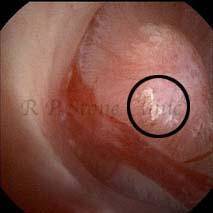

Kidney stone is a solid mass of CRYSTALS. It is the process of crystallization which initiates the formation of kidney stones. This happens in nephrons or units of kidney. Once a small crystal is formed, it can both grow & unite with other crystals leading to the formation of small concretion which eventually forms a stone. Once these large crystals detach from the collecting ducts, the process of stone formation starts in the renal collecting system. A recurrent kidney stone former is advised to know a little bit about something known as Randall’s plaque. Alexander Randall discovered plaques on the renal papillae eight decades back based on examination of 1154 pairs of autopsied Kidneys. He described these renal papillary lesions as cream colored or milk patch areas composed of calcium phosphate & calcium carbonate. These plaques could act as NIDUS for formation of KIDNEY STONE. Calcium Oxalate stone can form on this nidus & then detaches from this plaque to become a free floating stone in the collecting system of kidney

These images are taken as snap shots from the video recording of RIRS Surgery done at our hospital. These are Randall’s Plaques seen with Digital FLEX XC & Digital FLEX XC S. The cream or whitish patches are seen on the tips of RENAL PAPILLAE as seen in images below.

Randall’s Plaques may lead to the formation of Stones.

Those kidney stone patients who have Randall’s Plaques in their kidneys are more likely to form stones again (Recurrent Stones).

Stone Patients in whom Randall’s Plaques are detected at the time of RIRS Surgery should undergo regular ultrasound examination for early detection of stones.

Patients of Stones with Randall’s Plaques in their Kidneys should drink plenty of fluids in addition to Orange Juice & Lemonade.